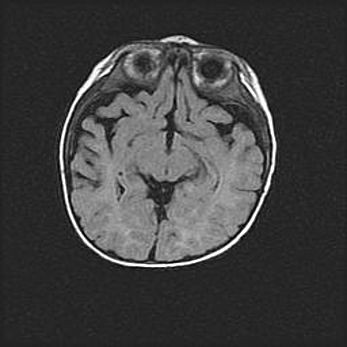

Наружная гидроцефалия с возможной атрофией височных областей.

Возраст: 28 дней

Вес: 3670 г

Пол: мужской

Окружность головы: 38 см

Срок гестации: 40 недель

Гидроцефалия головного мозга у новорожденных – это заболевание, которое характеризуется скоплением избыточного количества спинномозговой жидкости в желудочковой системе головного мозга в результате затруднения её перемещения от места выработки к месту поглощения в кровеносную систему или вследствие нарушения абсорбции. При открытой наружной форме гидроцефалии у новорожденных расширяются и переполняются субарахноидные пространства.

При нормотензивных  формах,  которые,  как  правило,  являются  следствием  перенесенных ишемических  повреждений  паренхимы  мозга,  возможно  сочетание микроцефалии  с нормотензивной гидроцефалией. В основе данных изменений лежит атрофия больших полушарий с преимущественной  локализацией  в  лобно-височных  областях.